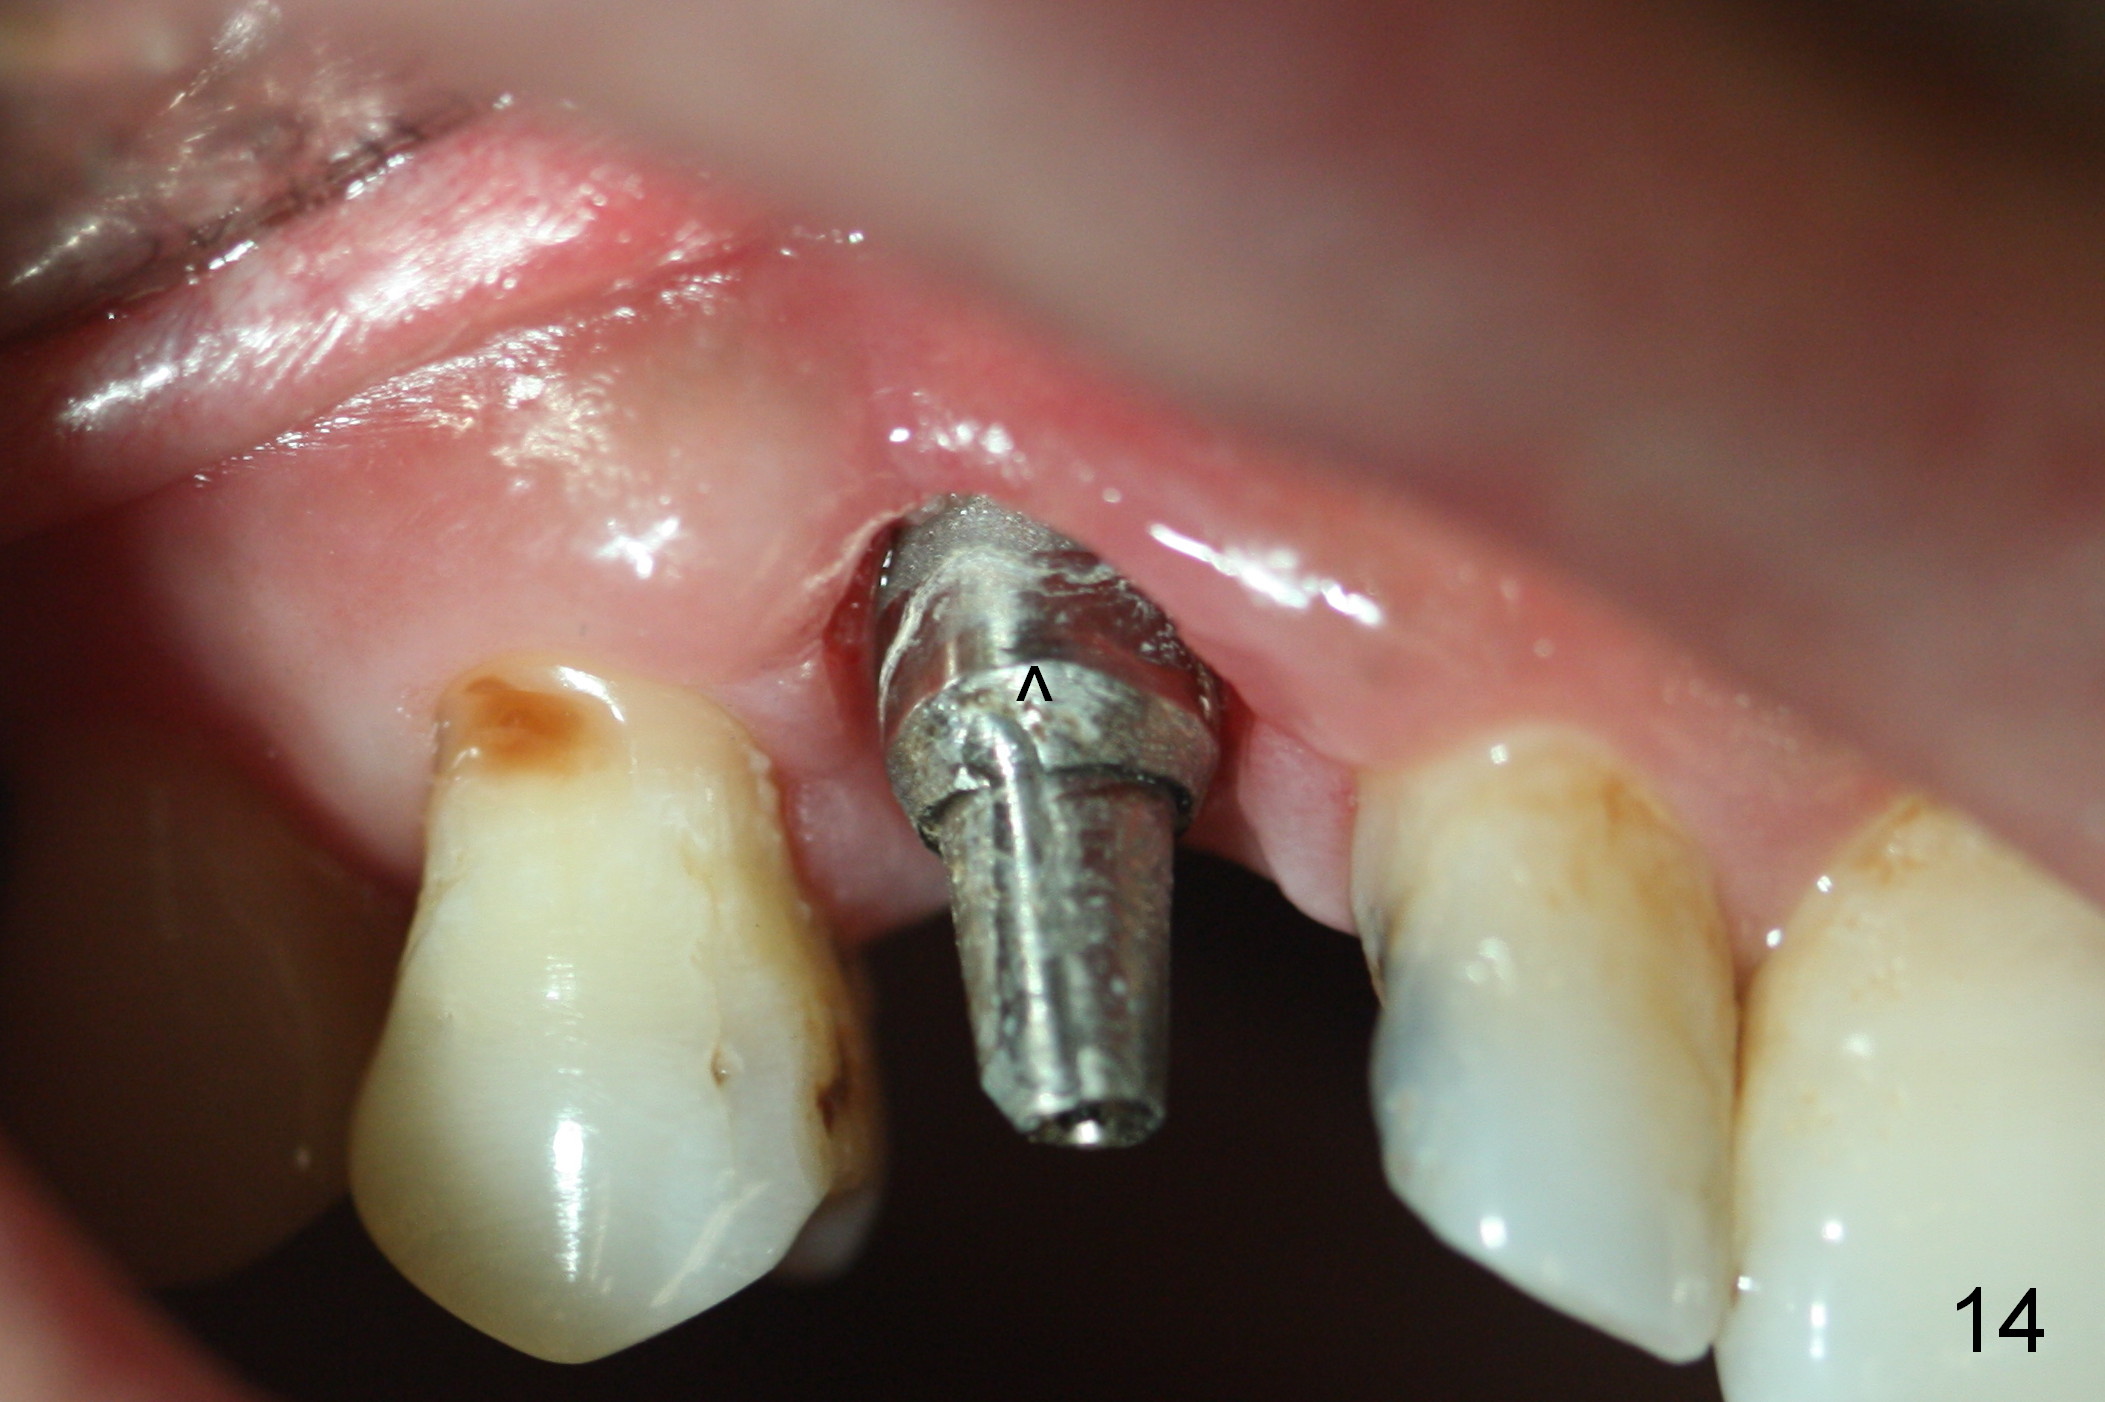

The patient returns 1.5 months postop. The provisional margin is much higher than that of the neighboring teeth (Fig.12,13: #6), unlike the opposite side (Fig.12: #11). When the provisional is removed, the implant margin is at the same level as that of the neighboring teeth (Fig.14 arrowheads). The implant margin is slightly extended apically (Fig.15 ^) prior to seating of the modified provisional. When the provisional is seated, its margin (Fig.16 ^) is at the implant margin; the gingival margin (*) is free and expected to move coronally by itself.